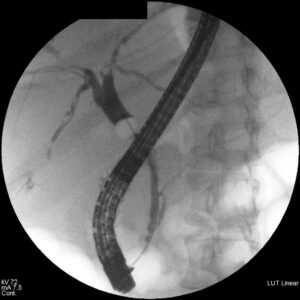

Además de realizar exámenes físicos y evaluar los síntomas de los pacientes, su médico digestivo también pueden recomendarle pruebas de diagnóstico. Pueden ser muy sencillas como un test de aliento: los hay para Helicobacter pylori, para intolerancia a la lactosa o para sobrecrecimiento bacteriano (SIBO). Otras pruebas, requieren una analítica de sangre: los niveles de transaminasas cuando sospechamos problemas en el hígado, o los marcadores tumorales son algunas de ellas. También solemos solicitar pruebas de imagen no invasivas (que no requieren introducir ningún aparato en el cuerpo): la ecografía abdominal es el ejemplo paradigmático. Pero también se incluyen aquí las radiografías de abdomen, los escáneres y las resonancias. Dentro de nuestra propia especialidad, las pruebas que hacemos los mismos especialistas de digestivo son de sobra conocidas: las endoscopias. Por la boca, las gastroscopias, las cápsulas, las duodenoscopias y las enteroscopias. Estas últimas permiten visualizar todo el intestino delgado. Por el ano, la colonoscopia y algunas enteroscopias, nos ayudan a determinar la causa de sus problemas digestivos.

En las enfermedades biliopancreáticas y algunos tumores asociados, la CPRE y/o la ecoendoscopia pueden ser mandatorias.